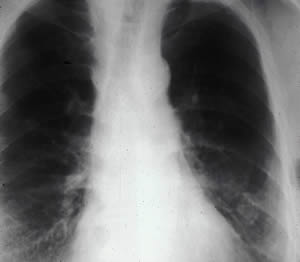

La asbestosis es una enfermedad que se produce a fuerza de inhalar fibras de amianto. El aire contaminado llega hasta los alvéolos del pulmón, donde queda retenido y termina produciendo rigidez en el pulmón e inutilizando las partes rígidas. Este proceso se denomina fibrosis, y la fibrosis pulmonar progresiva producida por el amianto recibe el nombre de asbestosis.

Pulmones afectados de asbestosis

Fotografía pulmones: Agency for Toxic Substances and Disease Registry.